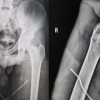

A 25-year-old male presented with complaints of right hip and thigh pain and swelling for the past 6 months. Previous history of falls from height 6 months back and he was treated with indigenous splinting for 6 months. He was barely ambulating with support for the past 6 months. Otherwise, the patient was healthy, non-smoker, and had no history of head injury. Clinically, the patient was unable to do SLR, with abnormal mobility over the distal femur and shortening of the right lower limb. Clinically, there are no signs of infection. The blood workup was unremarkable. X-ray showed the right neck of femur fracture non-union with the shaft of femur fracture non-union with gross over-riding of fracture fragments (Fig. 1). MRI was done which showed a viable femoral head.